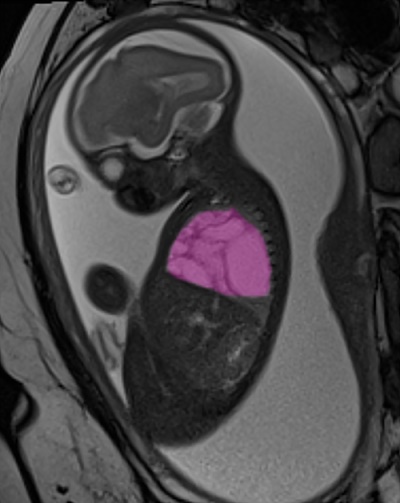

Durante la gravidanza, la diagnosi prenatale aveva rivelato una voluminosa cisti polmonare congenita di circa 9x6x5 centimetri (più grande di un’arancia), un volume tale da occupare quasi interamente la cavità toracica destra del feto e comprimere cuore e polmone di sinistra, con la conseguenza di un grave scompenso cardiaco fetale (idrope).

Il piano chirurgico e terapeutico per Alessandro e la sua mamma è stato realizzato grazie anche alla collaborazione con gli specialisti radiologi dell’Unità di Imaging Avanzato Cardio-toraco-vascolare e Fetale del Bambino Gesù, guidati dal dott. Aurelio Secinaro, che si sono occupati dello studio per immagini del caso (risonanza magnetica pre-natale e angio-TC post-natale) arricchito da ricostruzioni 3D.